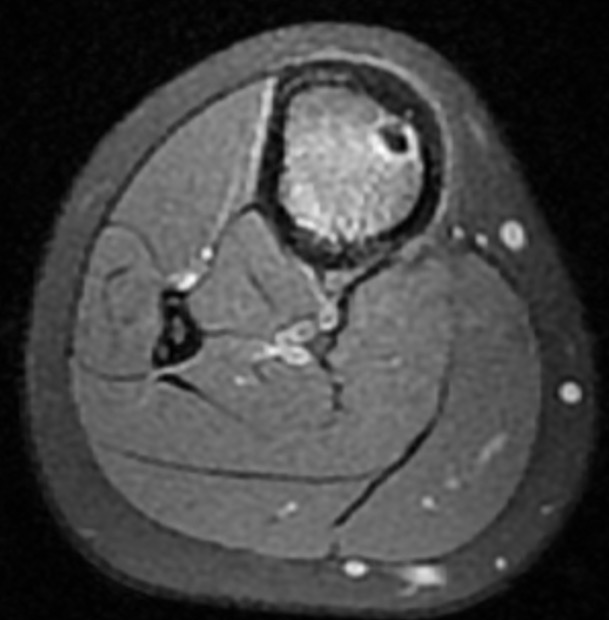

Osteoid osteoma femur